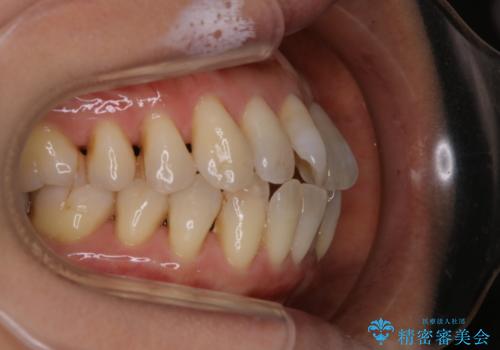

インビザラインによる非抜歯矯正を行いました。

IPRと呼ばれる、歯と歯の間を削る処置を行い、

がたつきを改善し歯を内側に入れることに成功しました。

今回のようなケースでは、

抜歯を行うことが困難であり、また歯ぐきと骨が薄いことで

拡大と呼ばれる歯のアーチを広げる処置を行うことも困難でした。

そこで、IPRによるスペースの確保をメインに行いました。